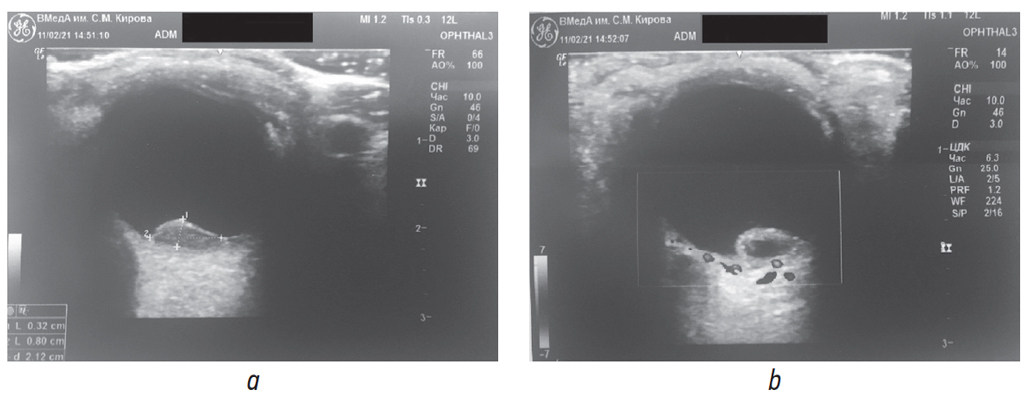

An ultrasound examination with a Doppler mapping in the lower part of the eyeball detected a rounded lesion of a heterogeneous echo density, which was 0.32 × 0.80 cm in the size and had no vascular signal in the center of the lesion (Fig. 2).

Fig. 2. Ultrasound procedure: a – B-scan mode; b – Doppler mapping mode / Рис. 2. Ультразвуковое исследование: а — режим В-сканирования; b — режим доплеровского картирования

OCT revealed a high elevation of the retinal pigment epithelium, and although its content could not be confidently differentiated, in combination with the presence of a subretinal blood, its hemorrhagic nature could be assumed. This was also confirmed by the ultrasound data which demonstrated a hypointense signal in the neoplasm center.